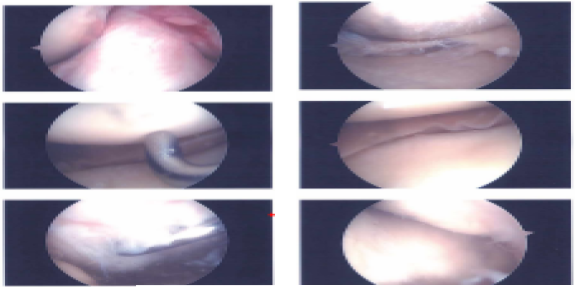

Examination of the medial tibiofemoral compartment showed a complex tear of the posterior horn of the medial meniscus along with grade 2 to grade 3 osteoarthritis of the medial femoral condyle.

Debridement of the meniscus was done with use of shaver and biters. Debridement chondroplasty was also performed with the use of a shaver. Examination of the intercondylar notch showed intact ACL. Examination of the lateral tibiofemoral compartment showed intact meniscus and cartilage.

Examination of the patellofemoral compartment showed grade 3 to grade 4 osteochondral lesion of the lateral facet of patella. Trochlea was intact. Debridement of the patella was done with the use of a shaver.

Arthroscope was inserted through the medial portal and shaver was inserted to the lateral portal and further balancing of the medial meniscus as well as chondroplasty of the patella was performed. Final pictures were taken and saved. Knee was thoroughly irrigated and drained.

Intraoperative images